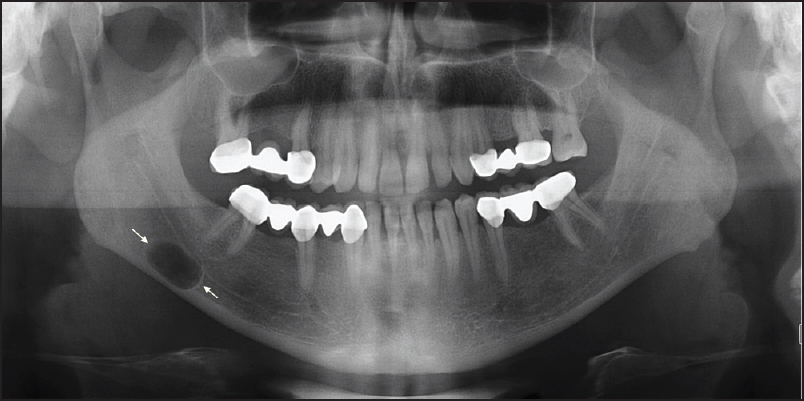

A radiolucent lesion was found incidentally on a dental panoramic radiograph in a 30-year-old man. The cyst was located in the mandible below the inferior alveolar canal. It was roughly oval in outline.

The appearance of a Stafne cavity on an X-ray can resemble that of a cyst, but there are some differences. Unlike cysts, Stafne cavities do not cause expansion or erosion of the surrounding bone. They usually have a well-defined and smooth appearance. It’s also important to note that Stafne cavities are typically found on one side of the mandible and are usually symmetrical.